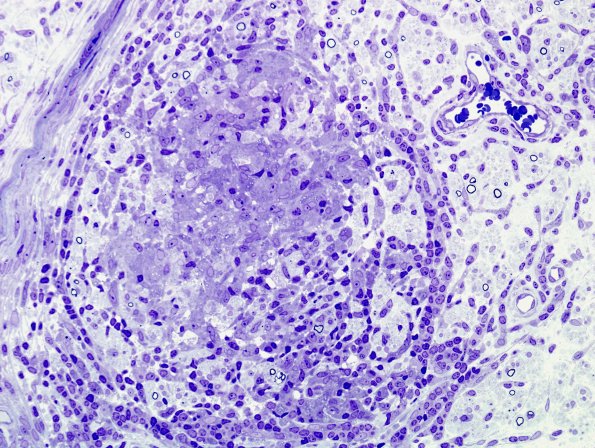

1B2B Leprosy, tuberculoid (Case 1) Plastic 11

Higher magnification of the granuloma of #1B2A> (Plastic section)